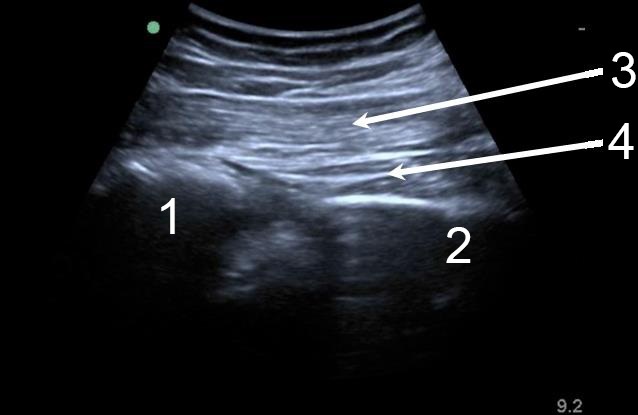

Hip Posterior Hip Soft Tissue 2 Image

Sacrum

Ischium

Gluteus Maximus

Gluteus Medius